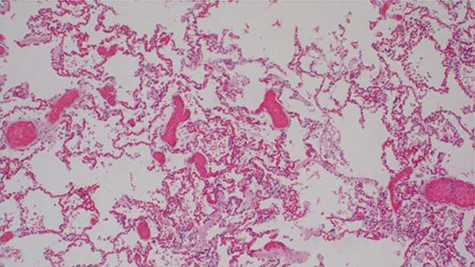

Histopathology analysis of the lung specimens revealed mixed chronic inflammatory infiltrates associated with pulmonary vascular thrombosis and areas of extensive necrosis (Figs 3 and 4). Bowel tissue sections revealed severe ischemic necrosis and mesenteric vessel thrombosis (Fig. 5). Thus, the primary causes of death were ruled to be ischemic colitis and pulmonary thrombosis due to COVID-19. The underlying disease conditions contributing to the cause of death being hypertensive heart disease, diabetes mellitus and septicemia.

Histopathology of lung tissue showing vascular thrombosis and extensive fibrosis and necrosis (hematoxylin and eosin ×40).